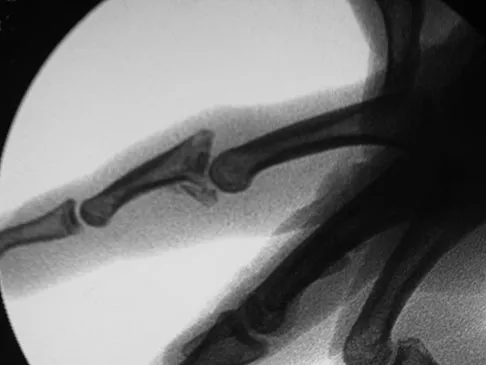

Question 37

A 7-year-old girl has had a painful forearm for the past 2 months. Examination reveals fullness on the volar aspect of the forearm. Radiographs and an MRI scan are shown in Figures 42a through 42c. Biopsy specimens are shown in Figures 42d and 42e. What is the most likely diagnosis?

Explanation